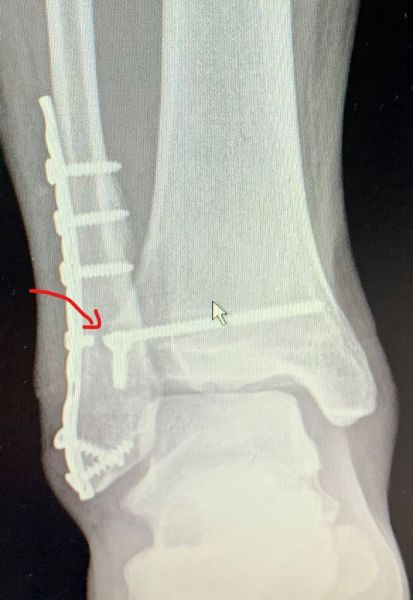

5. Delayed diagnosis of a lateral malleolus fracture in a 21-year-old male

Treatment: Open reduction internal fixation 20 days after the injury

I. Before surgery, lateral x-ray of the left ankle shows the site of fracture (red arrow) II. Four months post-surgery, lateral x-ray of the ankle shows the implant work with the union of the fracture (red arrow)